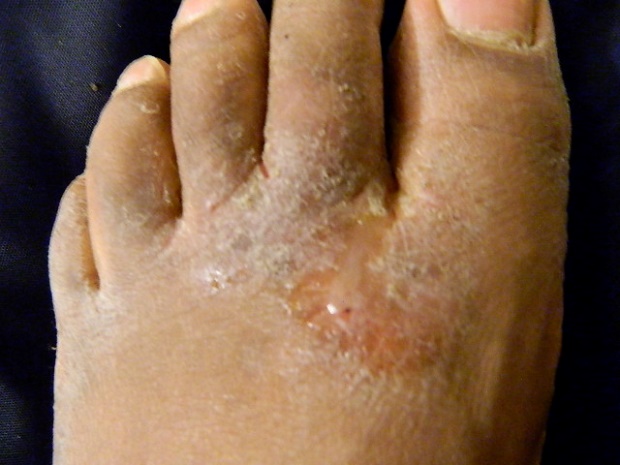

Tinea Pedis (feet, athlete’s foot)

Most common: interdigital tinea pedis (web space

of toes = scaly, peeling)

Third hyperkeratotic scale on the plantar

surface of the foot.

§ All types, the patient will complain of itching,

especially after removing their socks